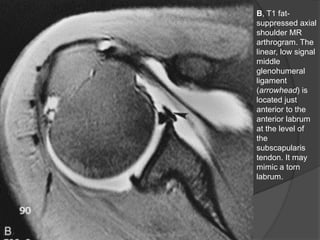

B, T1 fat-

suppressed axial

shoulder MR

arthrogram. The

linear, low signal

middle

glenohumeral

ligament

(arrowhead) is

located just

anterior to the

anterior labrum

at the level of

the

subscapularis

tendon. It may

mimic a torn

labrum.

• 55.

B, T1 fat- suppressedaxial shoulder MR arthrogram. The linear, low signal middle glenohumeral ligament (arrowhead) is located just anterior to the anterior labrum at the level of the subscapularis tendon. It may mimic a torn labrum. Dr. Emanuel R. Dantas